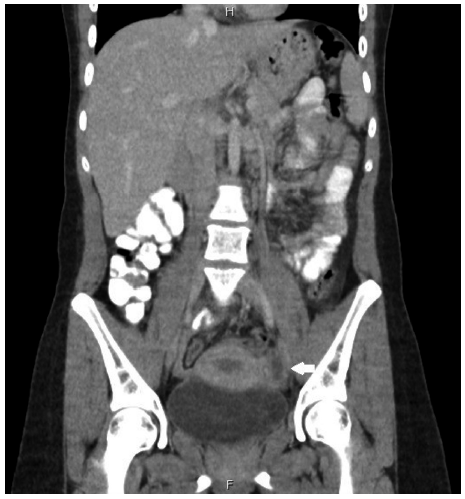

En el momento del examen físico no tuvo apariencia tóxica y los signos vitales fueron: presión arterial 110/70 mmHg, frecuencia cardiaca 89 latidos/minuto, frecuencia respiratoria 16 respiraciones por minuto y saturación del 98 % sin oxígeno suplementario. Presentó un abdomen blando, con heridas cicatrizadas de la cirugía de laparoscopia, sin distensión y con preservación de la peristalsis. El dolor era provocado con la palpación en el hipogastrio y en fosa iliaca izquierda, sin empeoramiento al rebote o sensación de masa. En la inspección pélvica se encontró un himen intacto. El resto del examen físico fue normal. Entre los paraclínicos de ingreso se documentó un hemograma con recuentos celulares dentro de la normalidad, proteína C reactiva elevada (24,15 mg/dl), bilirrubinas, transaminasas, ácido láctico y azoados sin alteraciones. Además, se obtuvo una prueba de embarazo con resultado negativo. Por el antecedente quirúrgico se sospechó una infección del sitio operatorio (ISO), por esto se solicitó una tomografía contrastada de abdomen (Figura 1).

Figura 1 Corte coronal de tomografía de pelvis. En la imagen se documenta un ovario izquierdo más grande de lo normal con pequeñas imágenes confluentes por hidrosalpinx.

En la imagen se observó el ovario izquierdo aumentado de tamaño con pequeñas imágenes confluentes por hidrosalpinx. Se concluyó que este podía estar relacionado con la cirugía abdominal previa. Se inició manejo con ceftriaxona y clindamicina. Sin embargo, a pesar de 48 horas del tratamiento antibiótico, la paciente evolucionó con fiebre, taquicardia, incremento del dolor y aumento del lactato sérico (2,6 mmol/L). Por esto se le administraron cristaloides intravenosos, se modificó la antibioticoterapia con piperacilina tazobactam y se llevó a laparoscopia. Como hallazgos intraoperatorios se encontró un absceso tubo ovárico izquierdo con severo proceso inflamatorio y sigmoides emplastronado; anexo derecho de aspecto normal. Se realizó una liberación de adherencias, drenaje de peritonitis y salpingooforectomía izquierda.